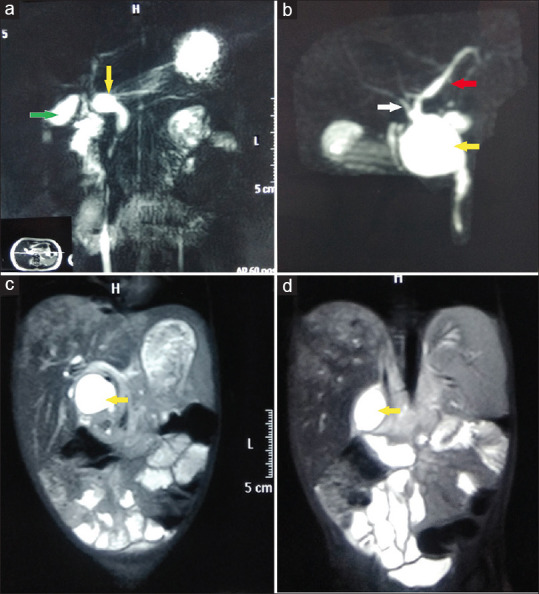

Results: A total of 74 patients were included in this study. There were 59 (79.73%) females and 15 (20.27%) males. Thirty-nine (52.70%) patients had jaundice at the time of presentation. Magnetic resonance cholangiopancreatography was performed in 57 (77.03%) patients following ultrasonography. Intraoperatively, malrotation was present in 2 (2.70%) patients. In our study, operating time ranged from 60 to 195 min (mean: 118 min). Hospital stays ranged from 8 to 17 days (mean: 11.5 days). The post-operative biliary leak was seen in 7 (9.50%) patients, out of which 6 (8.11%) minor leaks were managed conservatively. Roux-en-Y HJ was performed on 1 (1.35%) patient with a major leak. In our series, 4 (5.40%) patients developed cholangitis; post-operative haemorrhagic nasogastric aspirate 5 (6.76%), post-operative pancreatitis 3 (4.05%) and wound infection 4 (5.40%) were observed and managed conservatively. None of the patients in our study developed an anastomotic stricture, bile gastritis and adhesive small bowel obstruction.